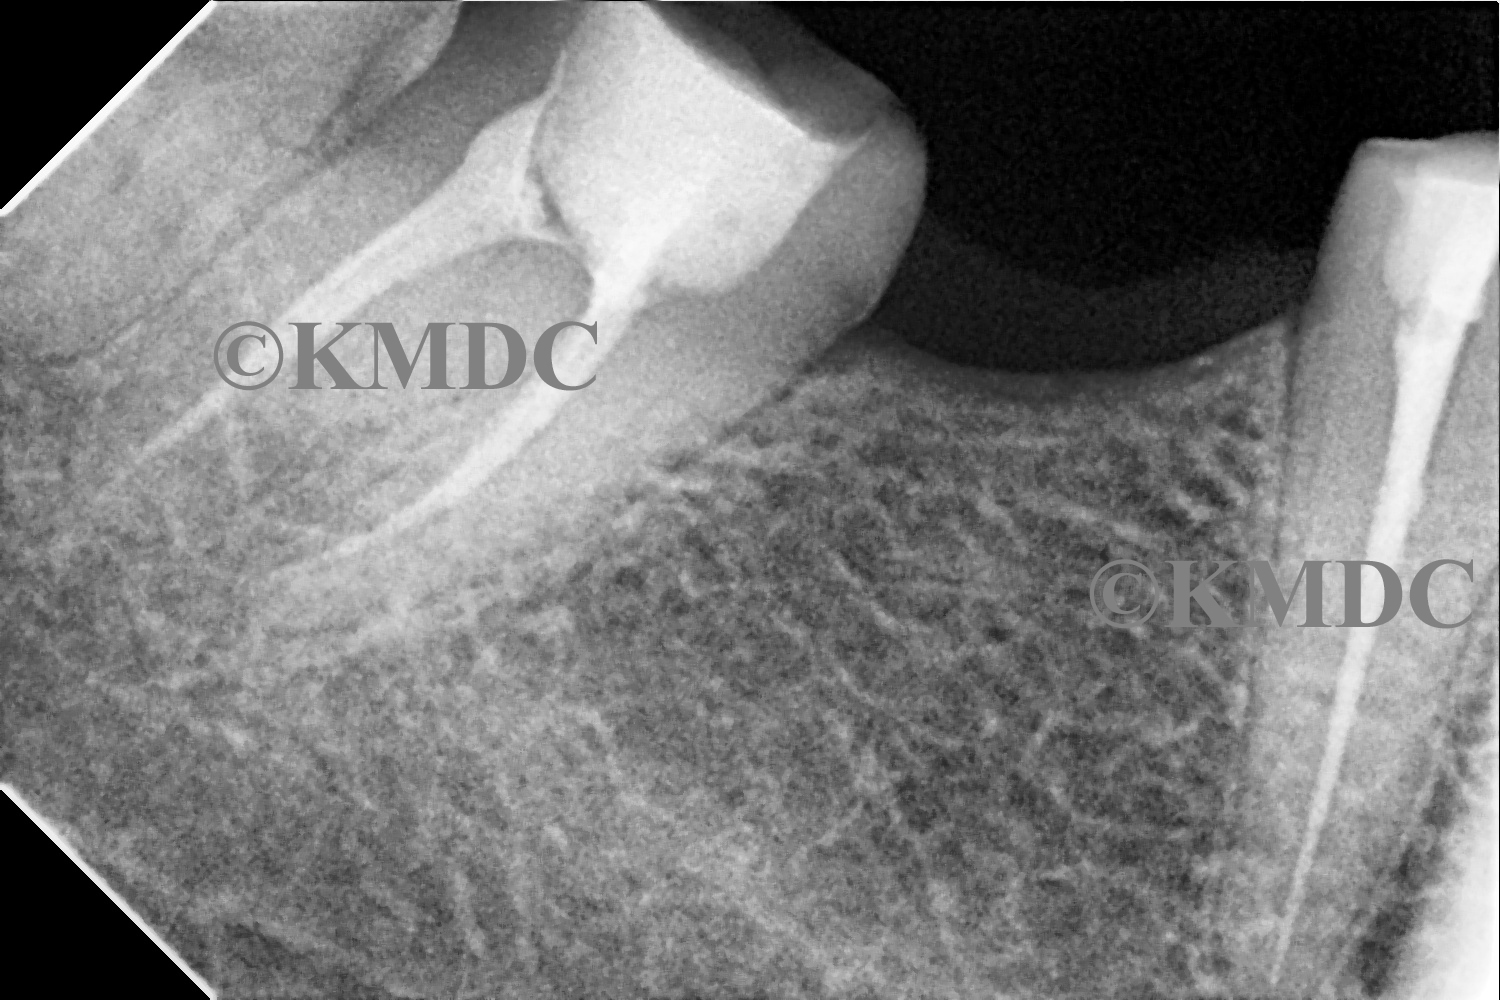

Clinical Gallery